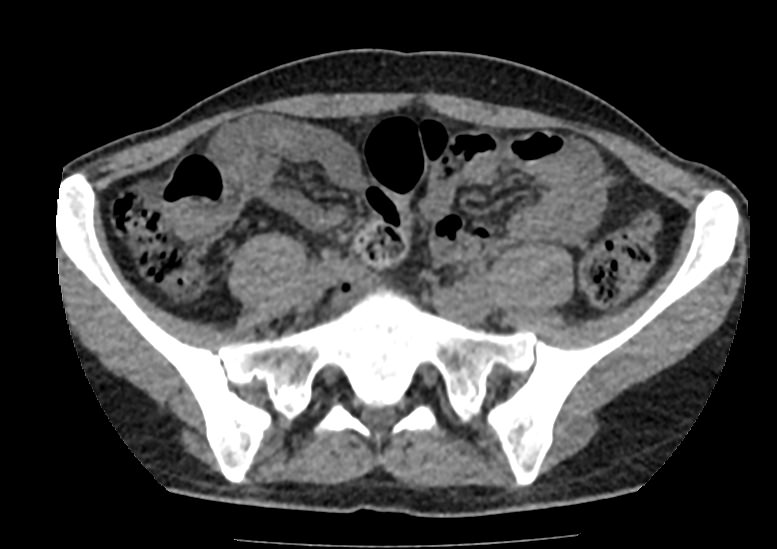

Мультиспиральная компьютерная томография позволяет детально оценить структуру лимфатических узлов, выявить ее неоднородность, определить точные размеры, выявить деформацию контуров, появление инфильтрации окружающих тканей с образованием цепочек, пакетов и конгломератов лимфоузлов.

Мультиспиральная компьютерная томография позволяет оценить структуру лимфатических узлов, обнаружить неоднородность, гиперплазию, деформацию их контуров.

Мультиспиральная компьютерная томография дает возможность визуализировать размеры лимфоузлов, их точную локализацию, взаимодействие с близлежащими органами и окружающими тканями, образование спаянных между собой инфильтратов лимфоузлов, выявить прорастание в окружающие ткани.